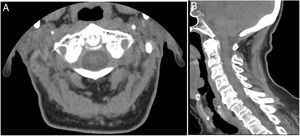

Cervico-occipital computed tomography (CT) demonstrated deposition of calcium pyrophosphate dihydrate crystals around the odontoid process of axis in a 87-year-old female patient with initial diagnosis of polymyalgia rheumatica (Fig. 1A, B). Patient had an acute severe cervico-occipital pain and markable neck stiffness. The patient had no shoulder or pelvic girdle pain and no jaw claudication. There is no history of trauma. There was a long personal history of knee pain due to calcium pyrophosphate dehydrate crystal deposition disease. Physical examination revealed limited passive cervical rotation without focal neurologic deficit. Laboratory results revealed elevation of erythrocyte sedimentation rate of 54mm/h and a normal C-reactive protein (5mg/dL). A knee radiography confirmed peripheral calcium pyrophosphate deposition disease. CT images showed atlantoaxial synovial calcifications in a crown around the odontoid process. A diagnosis of crowned dens syndrome (CDS) or periodontoid calcium pyrophosphate dehydrate crystal deposition disease was made. The patient was improved with a combination of prednisolone and nonsteroidal anti-inflammatory drug (NSAID) in a week. CDS is a rare clinical and radiological entity described firstly in 1985 and which pathophysiologic is not completely clear.1 This condition is accompanied by acute cervico-occipital pain and stiffness with severe limitation of neck rotation.2 The elevation of inflammatory markers is common.3 CDS can be misdiagnosed as various rheumatic diseases namely rheumatoid arthritis, spondyloarthritis, giant cell arthritis and PMR, as in our case.4,5 For diagnosis, cervico-occipital CT, showing calcification around the odontoid process, is the gold standard and should be done as soon as symptoms appear.6 Patients respond well to corticosteroids, NSAIDs and colchicine.6 Surgical procedure is performed rarely. CDS is a rare disease entity with various differential diagnosis. Thus, a high index of clinical suspicion is needed to obtain an early accurate diagnosis avoiding unnecessary exams or treatments.